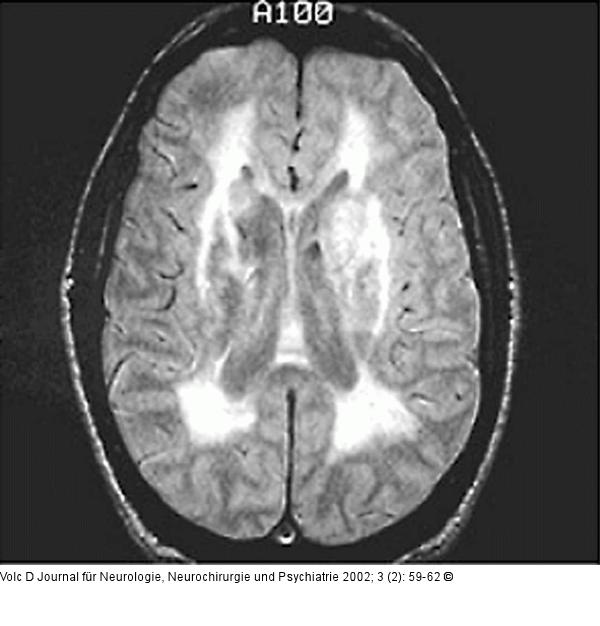

Abbildung 1: Morbus Binswanger - Demenz

Magnetresonanztomographie |